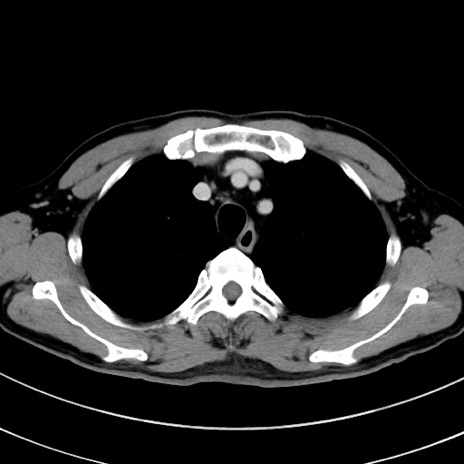

冠状断像

症例8(横断像)

【症例】 60歳代男性

【主訴】 黒色吐物

【現病歴】 4日前から嘔気自覚、2日前の朝食後にも嘔気あり、自分で手で嘔吐反射起こし嘔吐したところ血が混ざっていたため受診。

【既往歴】 5年前汎発性腹膜炎を伴う急性虫垂炎で手術、高血圧、前立腺肥大症、高脂血症

【身体所見】 腹部正中に手術癩痕あり 腹部平坦・軟圧痛なし膨満感あり

【データ】WBC 8400、CRP 4.54